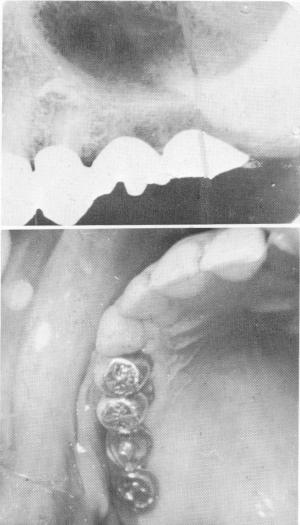

Fig. 15-58. The second premolar root is touching the floor of the maxillary sinus.

Fig. 15-59. An apicoectomy was performed on the root tip to make room between it and the antral floor. (From Linkow, L.I.: Atypical implantations for anatomically contraindicated situations, Dent. Concepts, Fall, 1967.)

2 Xray of second premolar root touching floor of maxillary sinus

3 Apicectomy on root tip creates space between it and antral floor